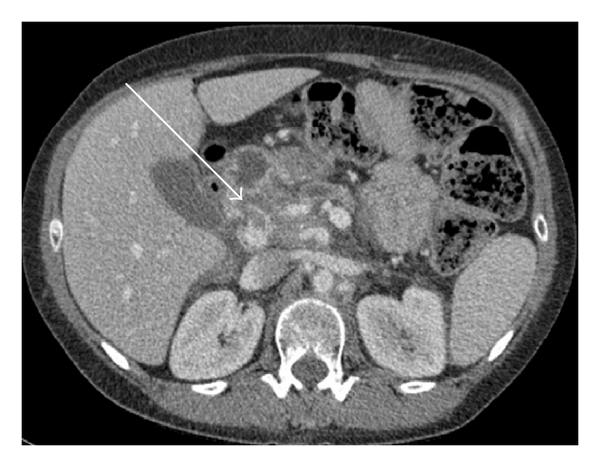

As Figures 1–5 demonstrate, the immediate postablation bed and zone are invariably larger than the original ablated tumor. We remain descriptive because the entire bed was extremely difficult to measure owing to the amorphous, irregular nature of the ablation. Moreover, the ablated tissue is not within an encapsulated organ; therefore, the ablation zone does not have defined borders as seen after, for instance, liver ablation. Four patients that showed continued stable disease are highlighted in Figures 1 through 4. An amorphous, hypoattenuating region with irregular shape persisted in subsequent CT scans in all patients with “stable disease.” Moreover, the ablation zone was typically smaller (due to decreased edema, hyperemia, and granulation tissue) than the immediate postablation bed in the following months and remained stable provided there was no recurrence. Imaging findings demonstrating recurrence are shown in Figure 5. Along with persistent irregular shape the ablation zone showed increased tumor bulk and extension as well as new mass effect (new narrowing of a blood vessel). Enhancement of the ablative bed was variable and often showed increased enhancement in the three-month and longer follow-up images. This was felt to be related to development of granulation tissue and fibrosis.

In our study, we found that the postablation bed is larger in volume than the initial mass. This is expected because it contains the tumor and the ablative margin. The postablation bed and zone appear irregular, amorphous, and hazy without margins or true boundaries. The ablation zone may decrease in size from the initial post-op bed to the initial surveillance study as the surrounding edema/fluid and inflammation resolve revealing the true ablation zone; however, as mentioned above, since there have been reports of an ongoing apoptotic process that persists up to 6–8 weeks after ablation, it will not be unusual to see some increase in volume in surveillance [19, 20]. Therefore, size is considered secondary in the CT evaluation for this reason and because the postablative bed/zone has poorly defined margins, making objective imaging assessment (size, attenuation) cumbersome. This may undoubtedly affect the accuracy and reproducibility of the measurement. Nonetheless, any increase in volume after stabilization of the postablation zone is considered worrisome for recurrence (Figure 5).